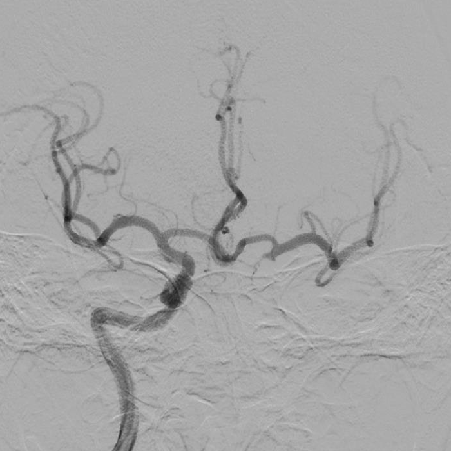

造影可见前交通动脉开放,双侧大脑中动脉显影,左侧颈内动脉末端显影;左侧颈内动脉颈段以远未见显影。

1、造影可见左侧颈总动脉和主动脉弓呈锐角,尝试泥鳅导丝+125cm多功能导管引导8F导引导管超选左侧颈总动脉时,导引导管无法送达,更换6F长鞘超选至左侧颈内动脉颈段,撤出导丝及多功能导管,考虑主动脉弓处张力较大,遂选择具有良好支撑性的React™ 68 远端通路导管替代中间导管。

React™ 68导管内造影见床突段显影浅单,以远未见显影

2、SWIM操作:0.014”微导丝+Rebar 18微导管通过LMCA M1段,手推造影剂示真腔,撤出微导丝,通过微导管将Solitaire 6-30支架输送至M1段,缓慢释放支架,远端在M1中段,近端在床突段,造影可见左侧前向血流部分恢复,眼动脉显影良好,眼动脉段可见充盈缺损。等待5分钟,推送React™ 68导管至支架近段,负压抽吸并缓慢回撤支架,然后撤出导管。可见支架体附着质软红色血栓,导管内抽出大量细碎的栓子。

3、造影可见左侧颈内动脉前向血流恢复,M1段以远显影良好,眼动脉段可见重度狭窄,观察5分钟后,再次造影,眼动脉段以远血流速度明显下降,局部造影剂滞留,考虑与对侧前交通动脉的代偿供血形成湍流,有再次形成血栓的可能,遂对狭窄部位进行球囊扩张。